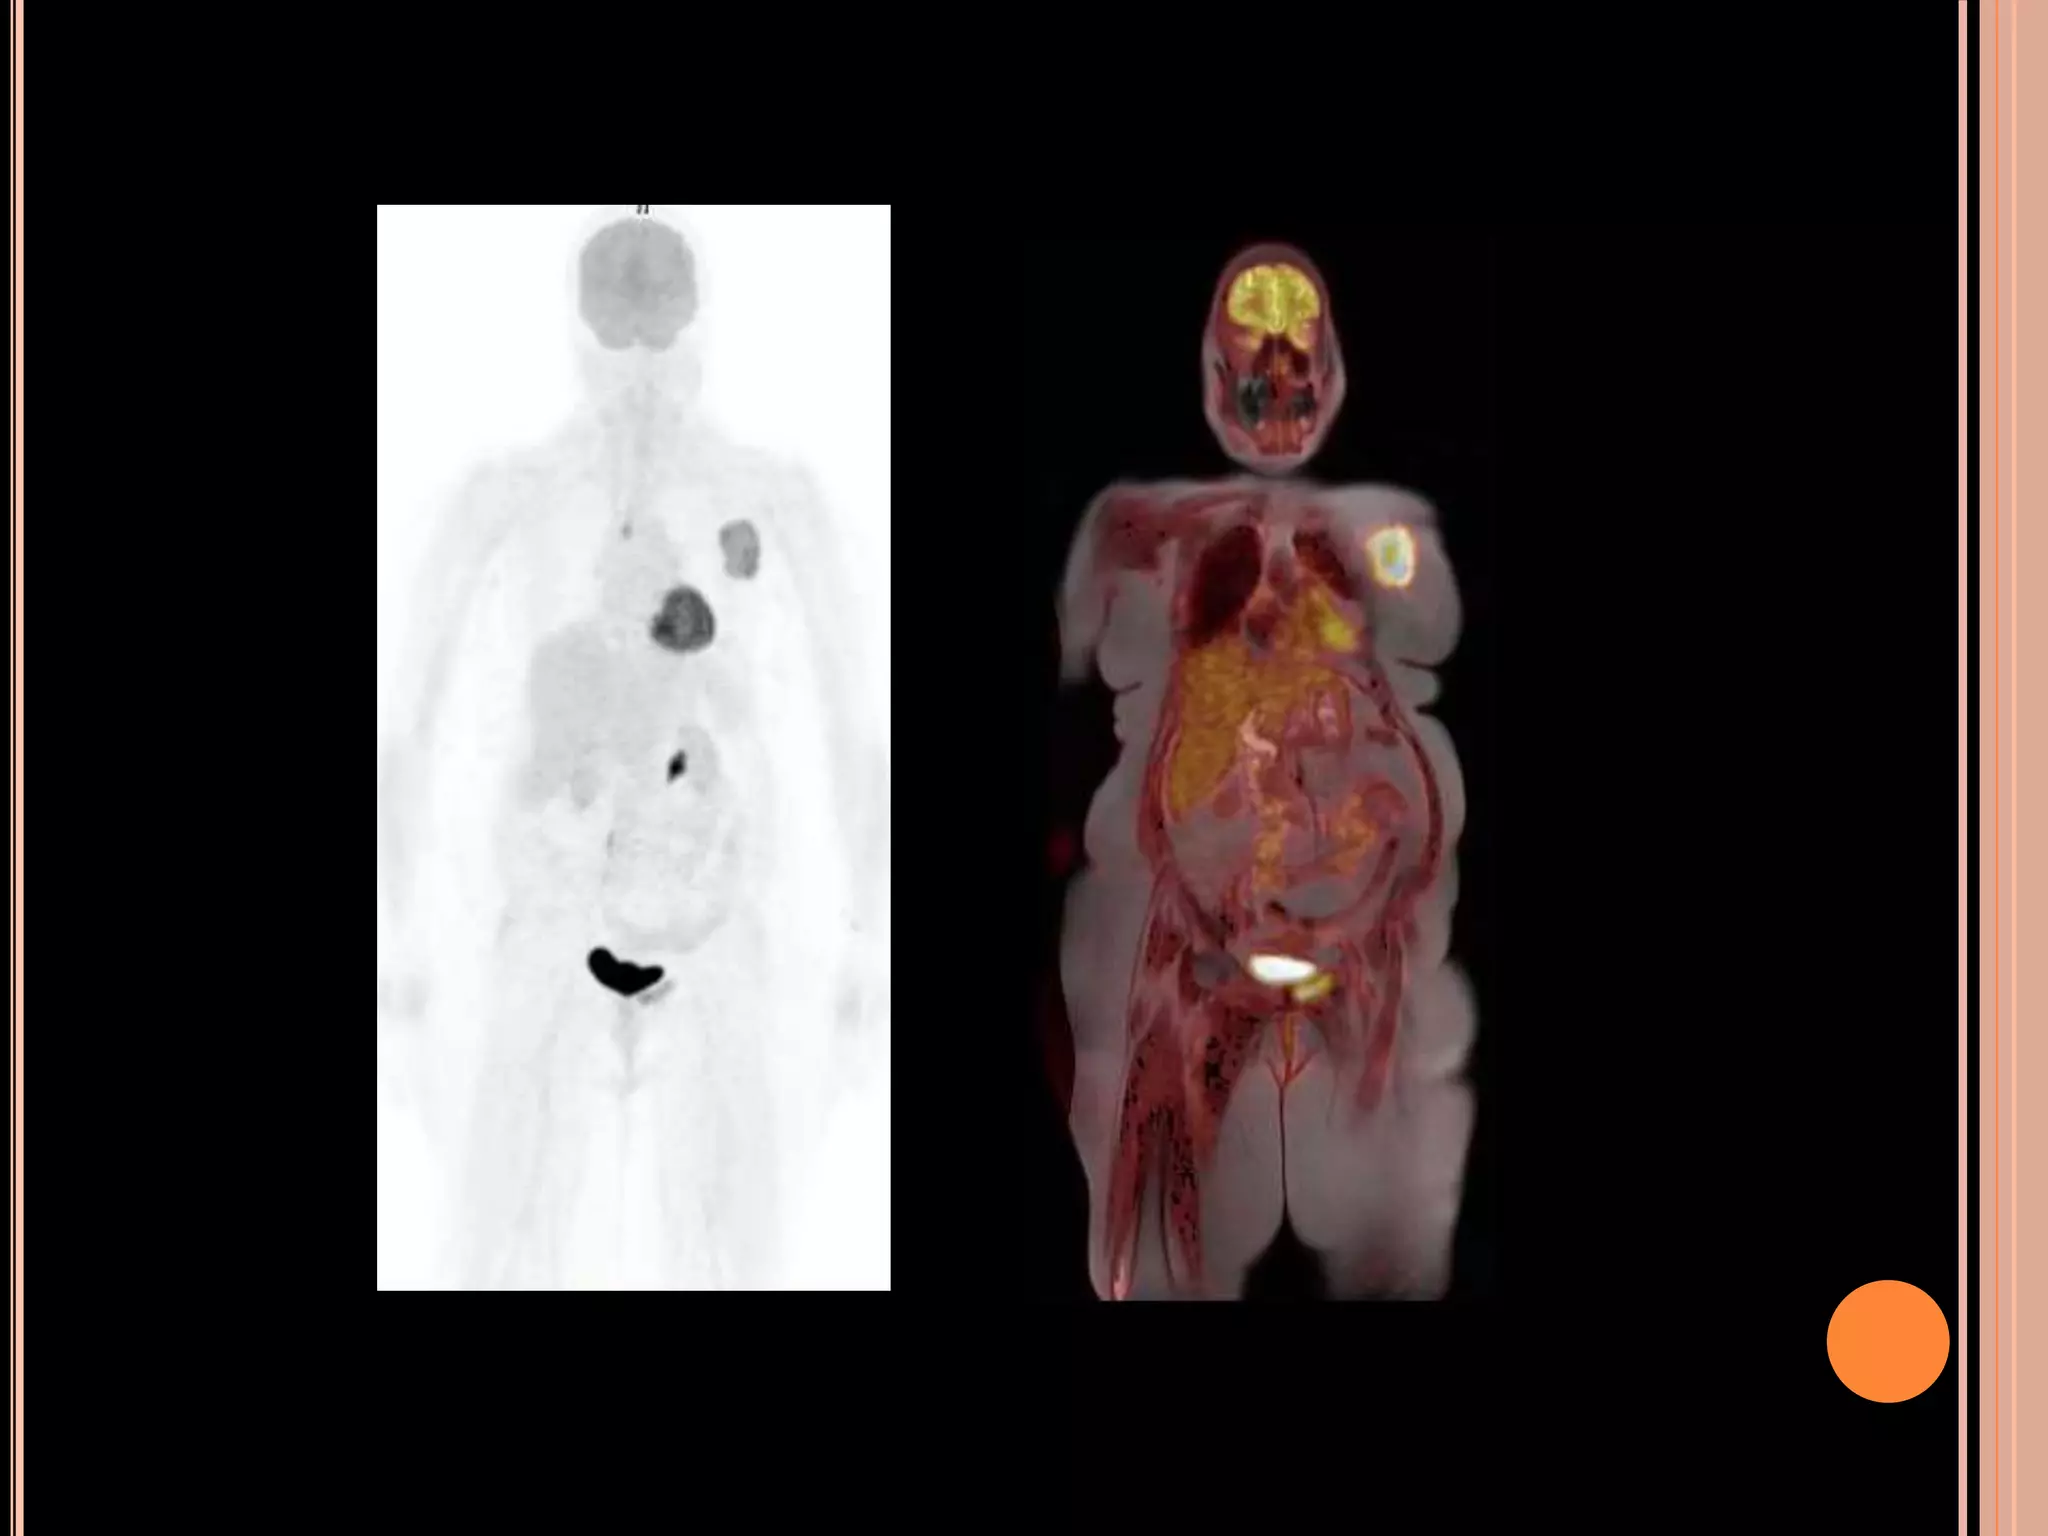

75- year old female, presented with left breast lump. FNAC from

the lump showed atypical cells.

Dynamic post contrast axial MIP image

Spiculated mass with intense FDG uptake.

FDG non avid small nodular enhancing lesion detected

in the right breast detected on MR I

FDG avid metabolically active marrow lesion in the left

pubic bone: definitive osseous metastasis

75- year oldfemale, presented with left breast lump. FNAC from the lump showed atypical cells. Dynamic post contrast axial MIP image Spiculated mass with intense FDG uptake. FDG non avid small nodular enhancing lesion detected in the right breast detected on MR I

FDG avid metabolicallyactive marrow lesion in the left pubic bone: definitive osseous metastasis